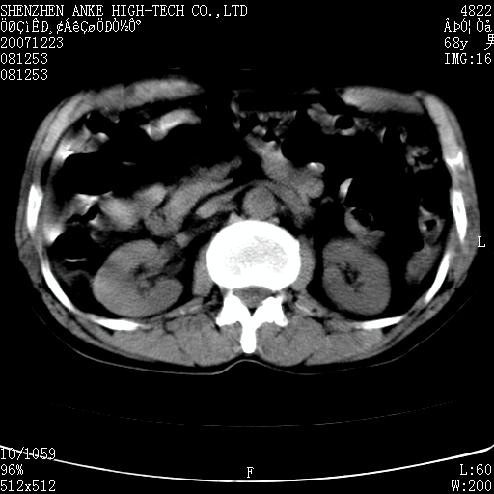

患者:男,63岁,2年前胆囊切除术后,现右上腹部剧烈疼痛近2天.

有无外伤史?右肾包膜下血肿可疑。

主要是问右肾有没有问题?患者无明显外伤史.

未见异常,病人差闭气,伪影较多.

肠道准备不好,干扰影大。

肠道气体伪影干扰太大了,应该是干扰所致,未见明显异常。

肠道准备不好,胃底后壁显示不清,右肾改变考虑为伪影。

上腹部ct平扫未见明显异常。(肠道气体较多,患者呼吸了)

请看第一张正位片,胸主动脉象有扩张,胸主动脉瘤?